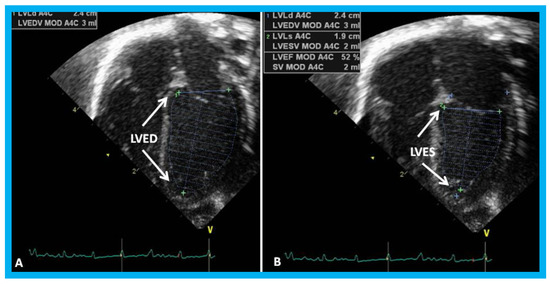

In a book chapter in the book titled Perinatal Cardiology: A Multidisciplinary Approach, echocardiographic evaluation of neonates with suspected heart disease was reviewed [32]. Initially, a brief review of principles of echo-Doppler technique was presented. M-mode and two-dimensional echocardiography, pulsed, continuous wave, and color-Doppler studies from standard views are recorded; subcostal views are most helpful in making a diagnosis in the neonate. In babies with important noncardiac causes of cyanosis or respiratory distress such as persistent pulmonary hypertension, neonatal asphyxia, central nervous system disorders, polycythemia, methhemoglobinemia, hypoglycemia, pulmonary hypoplasia, shock and sepsis, maternal drugs and others, the echo-Doppler studies are useful in confirming normalcy of the heart. The principles of estimation of pulmonary artery pressure were discussed. Then, evaluation of LV function was reviewed. Two easily usable and practical methods for the neonate are LV fractional shortening using M-mode echo (Figure 23) and LV area shortening by 2D echo (Figure 24). It is generally thought that the LV area shortening by 2D echo is better in assessing LV function than LV fractional shortening by M-mode echo, particularly in the neonate and young infant.

Figure 24. Apical four-chamber views of the left ventricle (LV) in end-diastole (LVED) in (A) and end-systole (LVES) in (B) demonstrating calculation of area shortening of the LV using Simpson’s rule: AS = (LVAd − LVAs)/LVAd (where AS is area shortening, LVAd is LV area in diastole, and LVAs is LV area in systole). The LV area shortening is 52% (see insert in (B)); normal values are 40 to 60%.